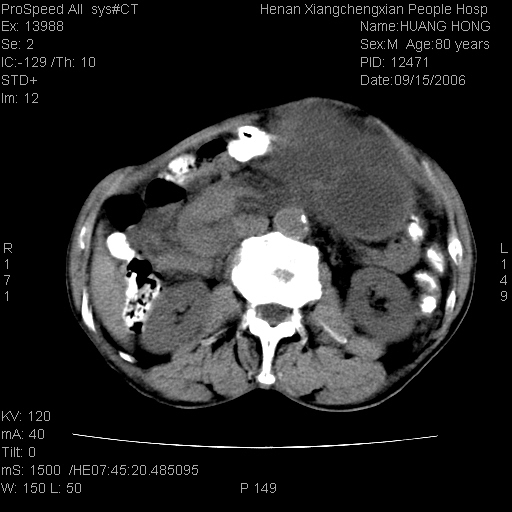

患者, 男, 80岁, 发现上腹部包块1年余,无其它不适.2006-9-14ct片是喝水后扫描2006-9-15ct片没喝水扫描![]() ![]() ![]() ![]() ![]() ![]() ![]() ![]() ![]() ![]() ![]() ![]() ![]() ![]() ![]() ![]() 以上是喝水片 以下是空腹片 ![]() ![]() ![]() ![]() ![]() ![]() ![]() ![]() ![]() ![]() ![]() ![]() ct:胰腺前方、肝脏与胃之间可见巨大类圆形囊性低密度影,大小约152mmx145mmx118mm,上缘平t11椎体上缘,下缘平l3椎体下缘,密度均匀,ct值15hu,其内呈多房分隔,囊壁薄且光滑,边界清晰,周围组织及器官明显受压。肝脏实质内未见异常密度影,胆囊未见异常,胰腺密度未见异常,脾脏大小、形态及密度未见异常,腹膜后间隙未见肿大淋巴结影。 印象:胰腺前方、肝脏与胃之间巨大类圆形囊性低密度影.性质待定。多考虑:.肠系膜巨大囊肿。 守望可可西里发言:支持楼主,考虑肠系膜囊肿,多为小肠系膜。 ysxyy发言:我总觉得这个病人虽然很像肠系膜囊肿,但还是应该强化一下; 下面这几幅图里肿块和主动脉的关系不太清,不知能否除外血管性来源? ![]() ![]() ![]() 病理结果:横结肠系膜间叶瘤.部分区域间质细胞增生活跃. 病理图片 ![]() 良性间叶瘤:是指由两种或两种以上的间叶组织所构成的混合性肿瘤.肿瘤仅发生在腹膜后和肠系膜,.前者较后者多发.良性间叶瘤常发生在肾或四肢,腹膜后较少见,各年龄均可发病.女多与男,预后较好,但术后易复法. 恶性间叶瘤:由两种以上恶性间叶组织成分组成. 光镜:肿瘤由脂肪/血管/平滑肌构成. 原贴地址: http://www.radinet.com.cn/forum_view.asp?forum_id=4&view_id=16217 ok |